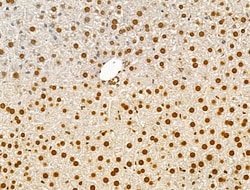

Invitrogen™ Phospho-AKT1 (Ser124) Polyclonal Antibody

Antibody detects endogenous levels of AKT1 only when phosphorylated at Ser124.

| Immunohistochemistry (Paraffin), Western Blot, Immunocytochemistry | |

| Human, Mouse, Rat | |